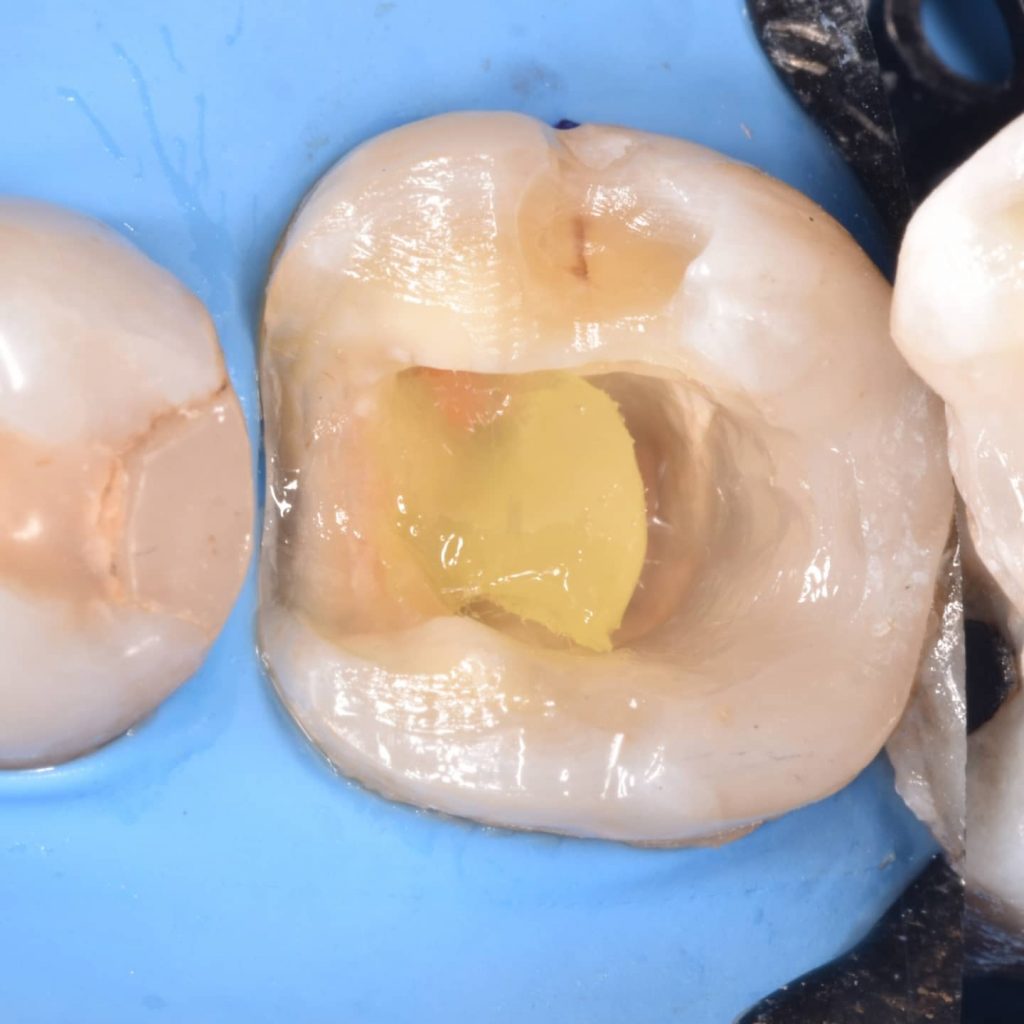

Ever x posterior for more support to the filling and for dentin replacement

Tooth preparation